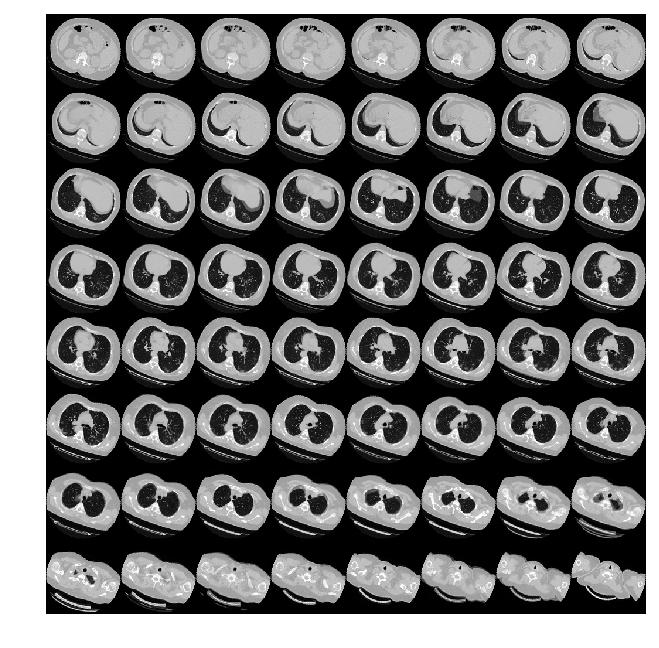

可视化增强型 CT 扫描。

images, labels = train_dataset.__getitem__(0)

print(images.shape)

image = np.squeeze(images, 3)

print("Dimension of the CT scan is:", image.shape)

plt.imshow(np.squeeze(image[:, :, 30]), cmap="gray")

plt.show()

(128, 128, 64, 1)

Dimension of the CT scan is: (128, 128, 64)

由于CT扫描有许多层切片,可视化多层切片。

plot_slices(8, 8, 128, 128, image[:, :, :64])